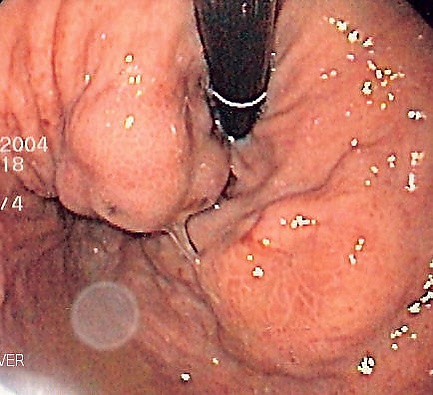

Диагноз варикозного расширения вен желудка часто ставится во время эндоскопии верхних отделов желудка[3]